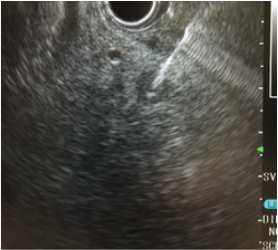

EUSは、内視鏡(胃カメラ)の先端に超⾳波観測装置(エコー)を装着しており、膵臓を最も詳しく観察できる検査機器です。5年⽣存率8%とされ、最も⼿ごわいと⾔われる膵がんも1cm以下で発⾒されれば、5年⽣存率は80%です。こうした早期の膵がんを⾒つけるのに不可⽋な最新鋭の検査がEUSです。その他にも、胆嚢がんと胆管がんの治療⽅針を決める上でも重要な情報を得ることができます。

超⾳波内視鏡で対象病変を観察しながら針⽣検を⾏うのがEUS-FNAです。これまで病理診断のための検体採取が難しいとされてきた腫瘤‧膵臓のリンパ節の検体採取が安全かつ簡便に⾏えます。サテライトでは世界トップクラスの実績を有する医師とそのチームが検査を担当します。

超⾳波内視鏡下針⽣検(EUS-FNA)による診断

9.6mmの膵臓腫瘍

胃の中から直接、細い針で腫瘍の組織を安全に採取しています